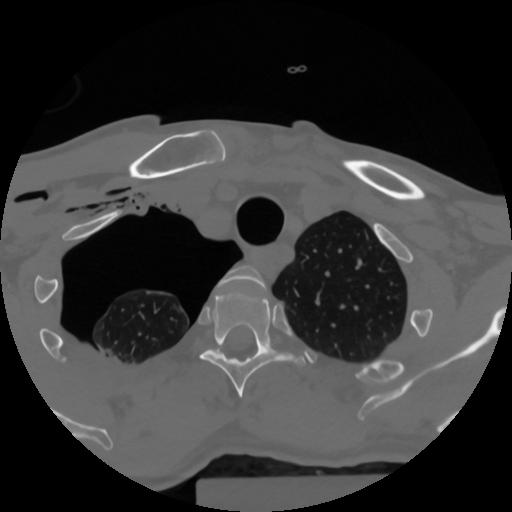

12 P.BLANDAS,,Vol,0.5,P.BLANDAS,,